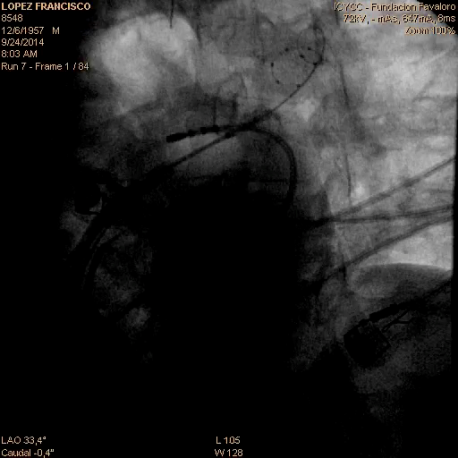

Crioablación con catéter balón. Es una tecnología que utiliza un catéter balón, el cual va plegado sobre un vaina, ingresando desinflado a la AI donde allí se insufla para ser colocado en la boca de cada vena pulmonar (en su desembocadura a la AI) luego de lo cual, cuando el contacto es adecuado se procede a enfriar en su interior mediante un gas que congela al balón y al tejido circundante produciendo una lesión por frío.

Figura III: a la izquierda esquema de ablación con criobalón. A la derecha imagen radiologíca observándose el balón con el sistema en la Vena pulmonar superior izquierda.